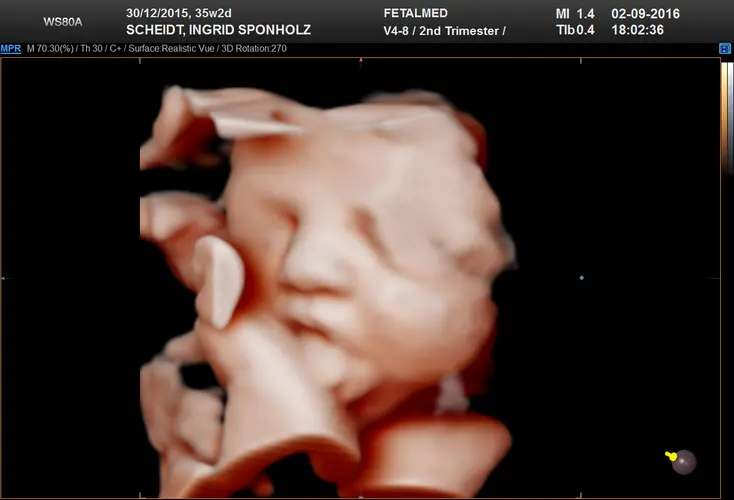

Parabéns! A partir desta semana, seu bebê é oficialmente considerado de termo completo. Isso significa que se ele nascesse agora, seria considerado um recém-nascido a termo, com todos os sistemas já suficientemente maduros para a vida fora do útero. Ele pesa aproximadamente 3 quilos e mede cerca de 48 centímetros, embora haja variações normais entre os bebês.

Seu pequeno continua ganhando peso steadily, acumulando aproximadamente 250 gramas por semana. A gordura subcutânea continua se depositando, criando aquelas adoráveis dobrinhas nos braços, pernas e pescoço que tanto amamos nos recém-nascidos. Essa camada de gordura não é apenas fofa – ela é essencial para a regulação da temperatura corporal após o nascimento. O corpo do bebê já consegue manter sua temperatura cerca de 1°C acima da temperatura materna.